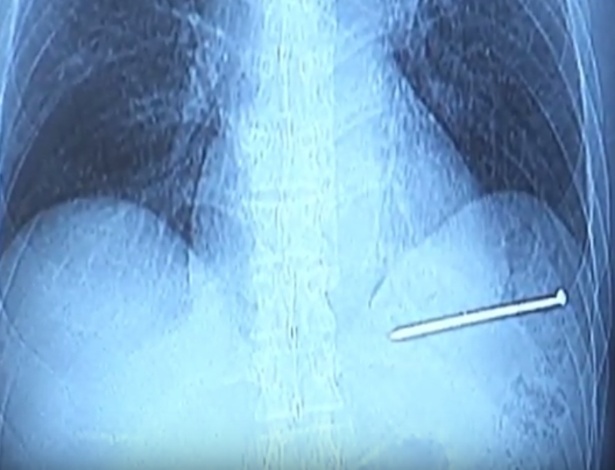

Segundo o site ‘UOL’, Doug Bergeson disparou acidentalmente uma pistola de pregos e acabou cravando um prego de quase 9 cm em seu peito.

De acordo com o site, o prego se mexia conforme seu coração batia, mas em vez de chamar o serviço de emergência, ele dirigiu por 19 km até o hospital mais próximo. Chegando ao hospital, Bergeson foi levado diretamente à sala de cirurgia.